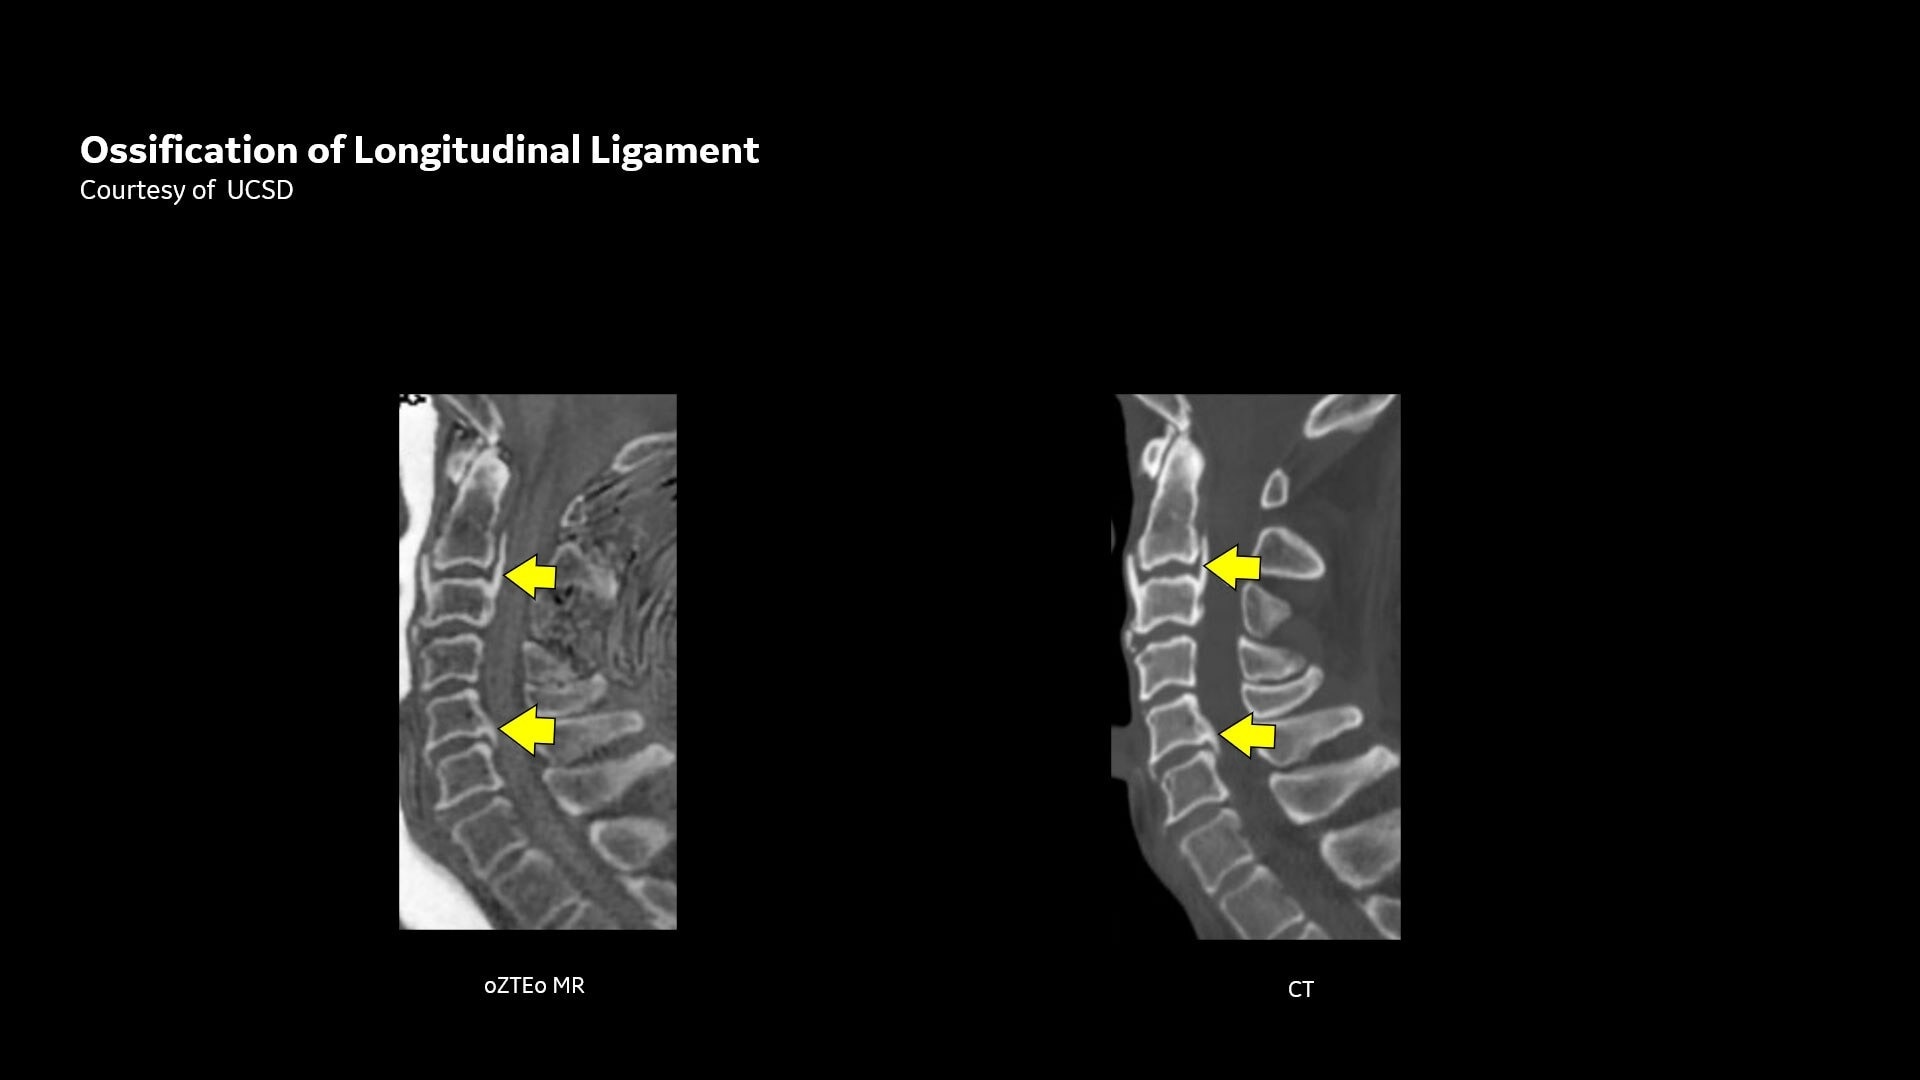

Available for all anatomies without ionizing radiation, oZTEo delivers images of bone morphology, calcification, ossification and fractures. oZTEo complements conventional MR soft tissue exams with perfect co-registration and provides 3D isotropic imaging using a radial ZTE acquisition, with inherent motion insensitivity. Use oZTEo with Volume Illumination for realistic 3D rendering.

MR bone imaging provides a CT-like image contrast without ionizing radiation, making it an attractive alternative for pediatric and pregnant patients where ionizing radiation is a concern. In addition, it provides a welcome alternative when longitudinal CTs are required, particularly when low-dose CT systems are unavailable.